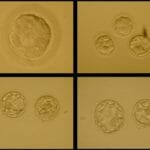

Cleavage Stage Embryo Grading